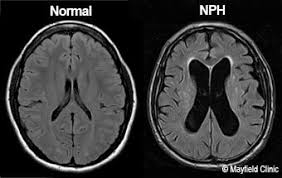

What are the 3 major symptoms associated with the condition characterized by the MRI below?

Hint: Elderly patients usually

What are Wet, Wobbly, and Wacky?

Associated w/ Normal Pressure Hydrocephalus.